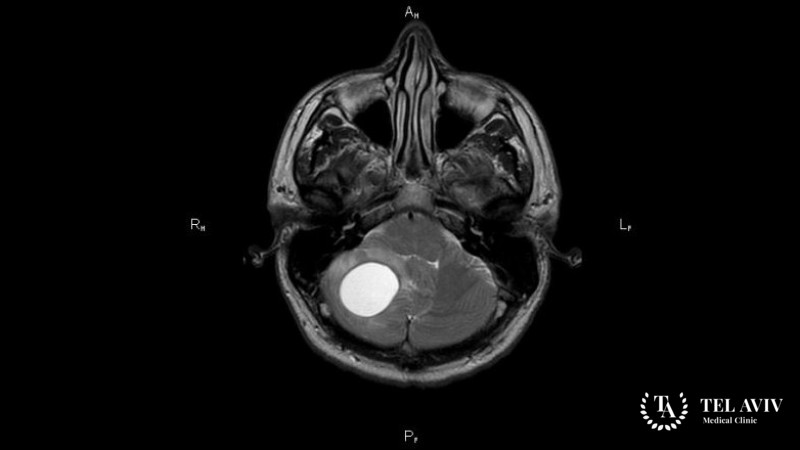

- Магнитно-резонансную томографию. Методика признана наиболее результативной при диагностике новообразований головного мозга. В ходе сканирования мозговой структуры формируется трехмерное изображение. Это позволяет эксперту изучить размер, форму, тип новообразования, состояние сосудов;